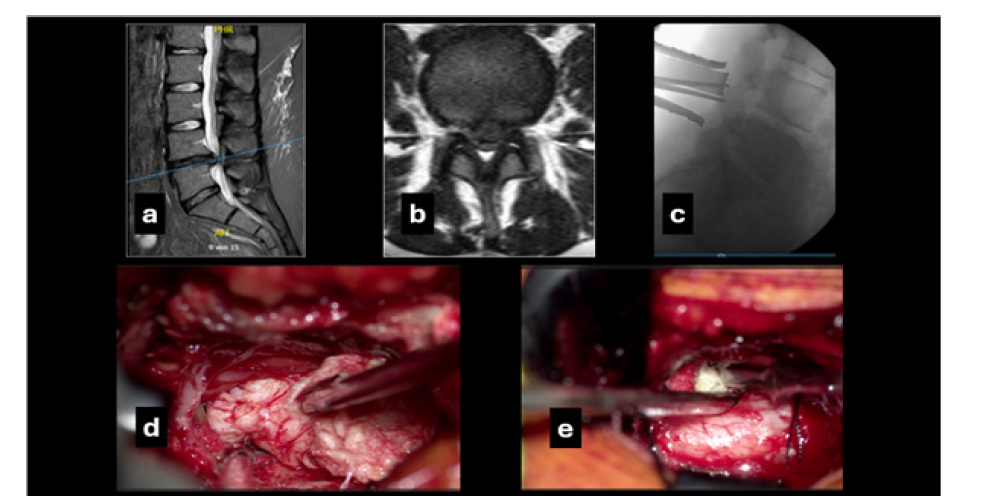

A 23-year-old obese female (BMI 35.8) was admitted emergently with severe low back pain (VAS 8) and left S1 sensorimotor deficit (VAS 9). She reported three months of progressive back pain and lower limb numbness, followed by one week of stress urinary incontinence. ODI was 87. Her medical history included depressive episodes with cyclothymia and posttraumatic stress disorder under treatment. Chronic opioid use and medication overuse were documented. Neurological examination revealed left L5-S1 hypoesthesia, reduced perineal sensation and left foot plantar flexion weakness (3/5). MRI showed progression of a previously identified L4-L5 disc herniation with subtotal canal obstruction, classified as type 3A (AFFM-YOLOv8). Surgery was performed urgently. The procedure was technically successful and complication-free. Although medication overuse required gradual regulation, neurological deficits almost completely resolved postoperatively. ODI after rehabilitation was 39. VAS improved to 4 for back pain and 3 for leg pain, accompanied by progressive weight reduction (Figure 2).

Figure 2:The preoperative T2W magnetic resonance imaging mid sagittal (a) and axial (b) views showing the massive disc herniation at the level L4-L5; (c) intraoperative lateral X-ray showing the unilateral muscle retractor and a Kocher clamp applied to the L4 lamina to confirm the level of access. Intraoperative photomicrographs: (d) shows how the sequestered disc tissue can be progressively and ipsilaterally removed in one large block with a disc forceps and without additional retractions; (e) after tilting the table about 25 degrees and positioning two cotton pads above and below the contralateral disc space and only aided in retraction by the tip of the suction device, the residual protrusion of the posterior longitudinal ligament is being incised with a scalpel to extract the herniated disc.